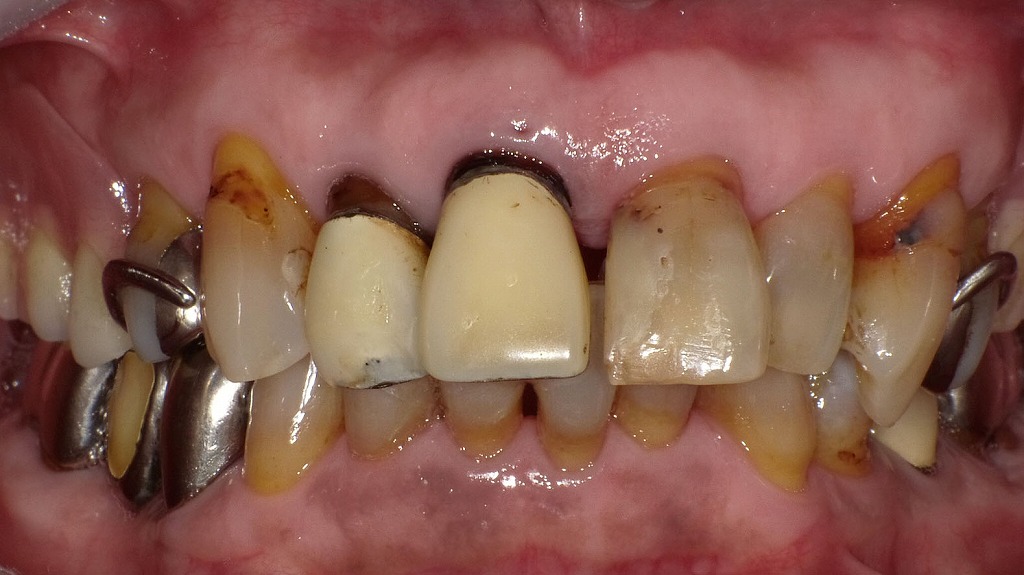

上顎前歯の補綴物周囲にみられる歯頚部トラブルとう蝕🦷

上顎右1・2番に硬質レジン前装冠が装着されており、歯肉退縮により歯頚部の露出と歯根部の黒変が認められます。周囲の天然歯には歯頚部う蝕も確認できます。撮影前にはエアフローによるクリーニングを行い、歯面のステインやバイオフィルムを除去した状態ですが、それでも歯頚部の問題が明瞭に確認できる症例です。補綴物の適合性や歯周環境の重要性が示唆されます。